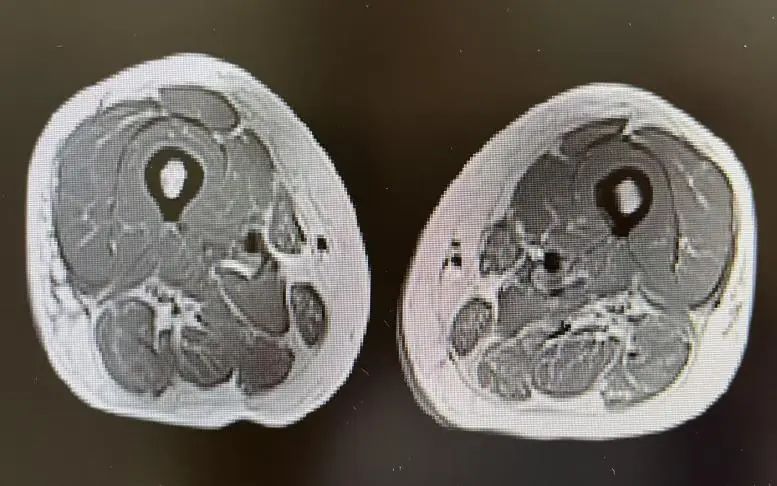

接诊时,李女士的情景很是危险。风湿免疫科主任庄宇、张雪珍副主任医师经详备问诊和针对性查验后,马上捕捉到重要信息:肌肉无力致行走艰难、吞咽艰难激发呛咳、呼吸艰难领导肺部受累;血液检测中,肌酸激酶(CK)高达 14314 U/L,远超浅显值百倍;勾通特异性抗体(抗 SRP 抗体)阳性等成果,会诊指向了不吉的免疫介导坏死性肌病(IMNM)——这是一种进展迅猛、可累及呼吸、吞咽及心肌的危重自己免疫性疾病。